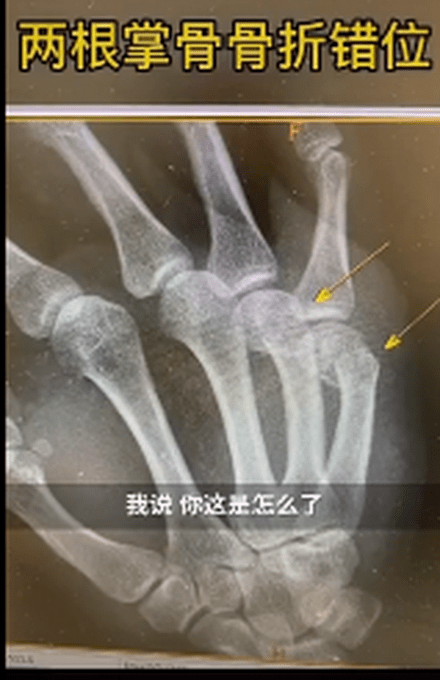

父亲辅导作业捶墙致手骨折!

近日,上海新华医院骨科接诊了一男性患者 。该患者右手第四第五掌骨肿胀明显 。新华医院骨科主治医师王晖询问后得知,原来这名患者是在家辅导孩子作业时,因孩子作业做得不理想,生气但舍不得打孩子,自己捶墙,没想到把自己捶骨折了 。